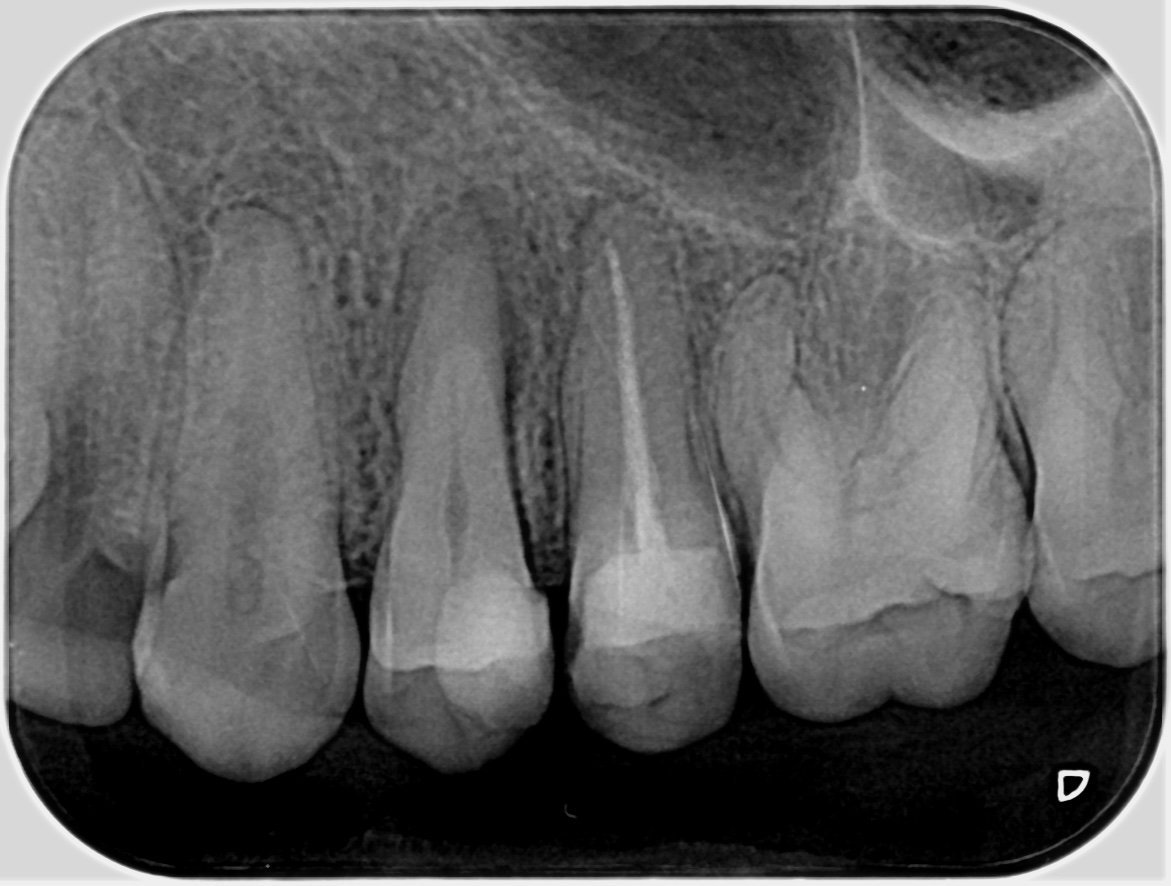

Кое е по-добро - импланти или мостове?

Имплантите и мостовете имат своите предимства и недостатъци. Имплантите често се рекламират, но не винаги са успешни в дългосрочен план. Те изискват определени условия на организма, които могат да увеличат шансовете за успешно интегриране в костта. Освен това поставянето на имплант може да бъде по-скъпо и не гарантира по-голям процент на успеваемост. Мостовете, от друга страна, могат да бъдат поставени по-бързо и по-евтино, но изискват изпиляване на съседните зъби. Всеки случай трябва да бъде оценен индивидуално от имплантолог, който може да предложи най-подходящото решение за конкретния случай.